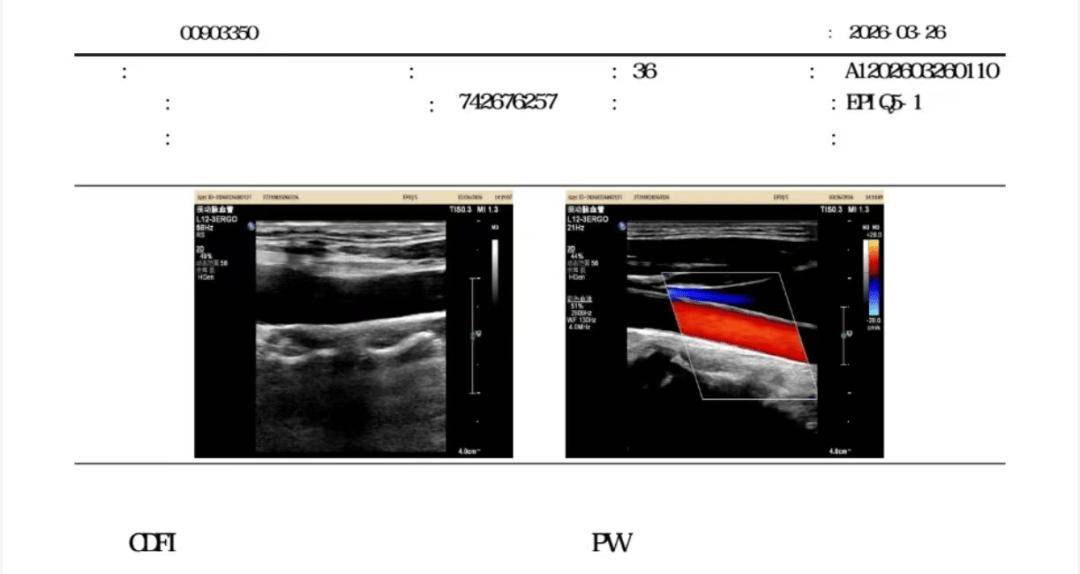

主要问题:因长期熬夜(每日凌晨 1-2 点睡)、久坐、精神压力大,体检发现颈动脉斑块 7.1mm*1.8mm,丙氨酸氨基转移酶、天门冬氨酸转移酶、总胆固醇水平升高。

3个月后复查:斑块完全消失!

坚持干预 3 个月后,体重仅仅下降1.5kg,但颈动脉B超显示7mm斑块彻底消失,查血显示丙氨酸氨基转移酶、天门冬氨酸转移酶、总胆固醇水平降至正常。